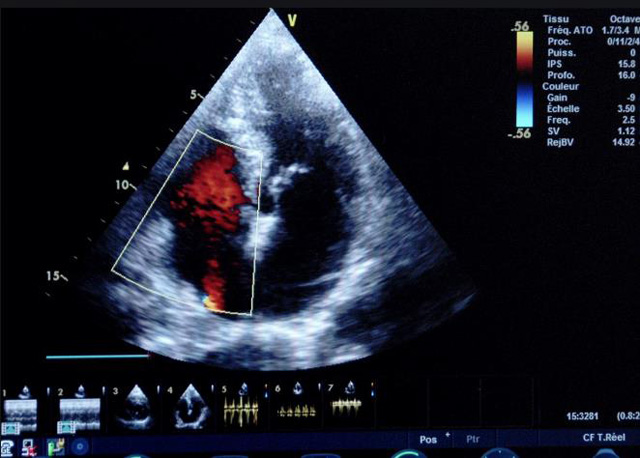

二、彩色室壁运动分析

(一)基本原理彩色室璧运动分析,从整体散射数据中识别心内膜边界,并与前一帧彩色不同,心脏收缩或舒张期开始到结束时心内膜的全部过程。每一次顺序显示结束后,原来的彩色自动消失,以便进入下一个显示过程。其结果是获得对应于每一个心动周期的彩色显示,描绘特定周期内室壁运动的时间运动轨迹。

(二)操作步骤根据背向散射数据中将心内膜运动的位移过程分类为组织或血液的原理,边缘检测跟踪心内膜和血液的界面。橙色表示收缩期的开始,收缩期不同时相逐帧显示色彩均叠加在收缩末期最后一帧图像中。检查时,可按以下步骤进行:

①显示较为理想的二维图像,常用切面有心尖四腔心、二腔心、左心室长轴和左心室乳头肌水平短轴切面。

②启动AQ系统,启动后适当地调节增益补偿,显示心内膜。

③启动CK系统,启动后划定感兴趣区域。同时记录的心动图R波顶点为舒张末期,T波终点为收缩末期,显示RT间期的CK彩阶图,连续记录3~ 5个心动周期。

(三)检测节段性室壁运动异常,研究冠心病患者左心室功能和分析局部室壁运动过程中。测量每一节段室壁的运动量,运动正常的节段彩带色彩均匀层次光整。运动减弱的节段,厚度薄层次不全。心内膜位移幅度和速度均减低。心内膜位移幅度和速度甚低或难以测得。正常的多层彩带消失,呈现红色色带,心内膜位移呈负向,幅度和速度亦减低。急性心肌梗死的患者中可用于识别存活心肌抑或坏死心肌。多巴酚丁胺负荷试验存活心肌的心内膜位移幅度增高,停药后即消失,而坏死心肌则无上述表现。实时检查冠心病的节段性室壁运动异常,有时候通过发现局部心肌运动的时相异常,对于心脏传导障碍的诊断也可能有帮助。